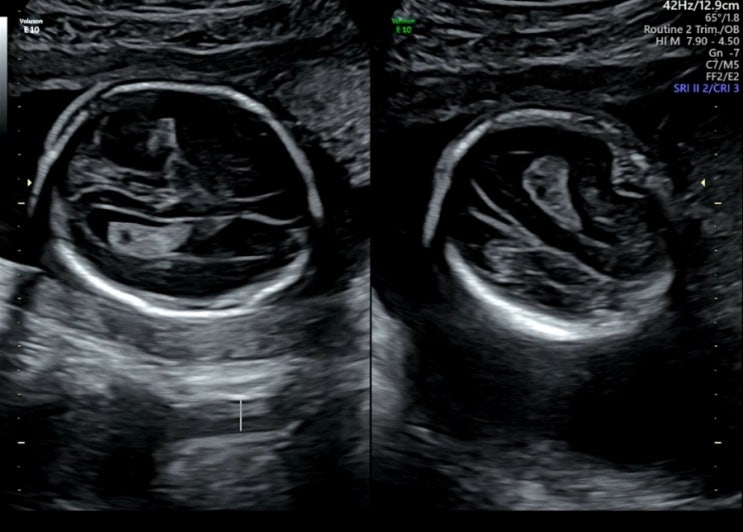

임신기록 - 20주, 24주 진료 (맥락막총낭종, 임당검사)

임신 20주 & 24주 진료기록 시간이 진짜 빠르게 간다. 한 달에 한 번 꼴로 진료를 보러 가는데, 벌써 2...